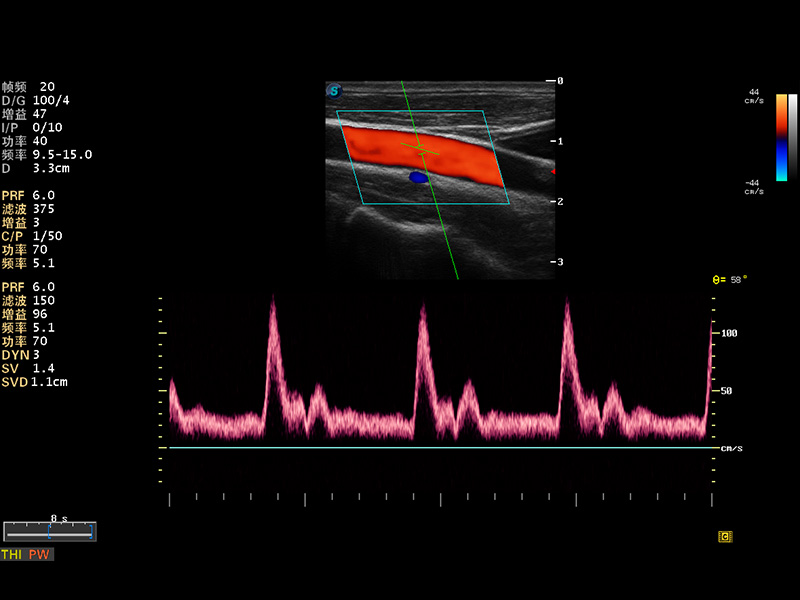

S8 EXP便携式彩色多普勒超声诊断仪是DB中国旗舰官方网站研发的高端全身应用型便携彩超。高通道的VIS平台融合可视化(Visual)、智能化(Intelligent)和人性化(Smart)的特点,配以DB中国旗舰官方网站自主研发生产的探头大家族,使您能够快速、准确的获得病人信息,提高工作效率的同时减轻疲劳。